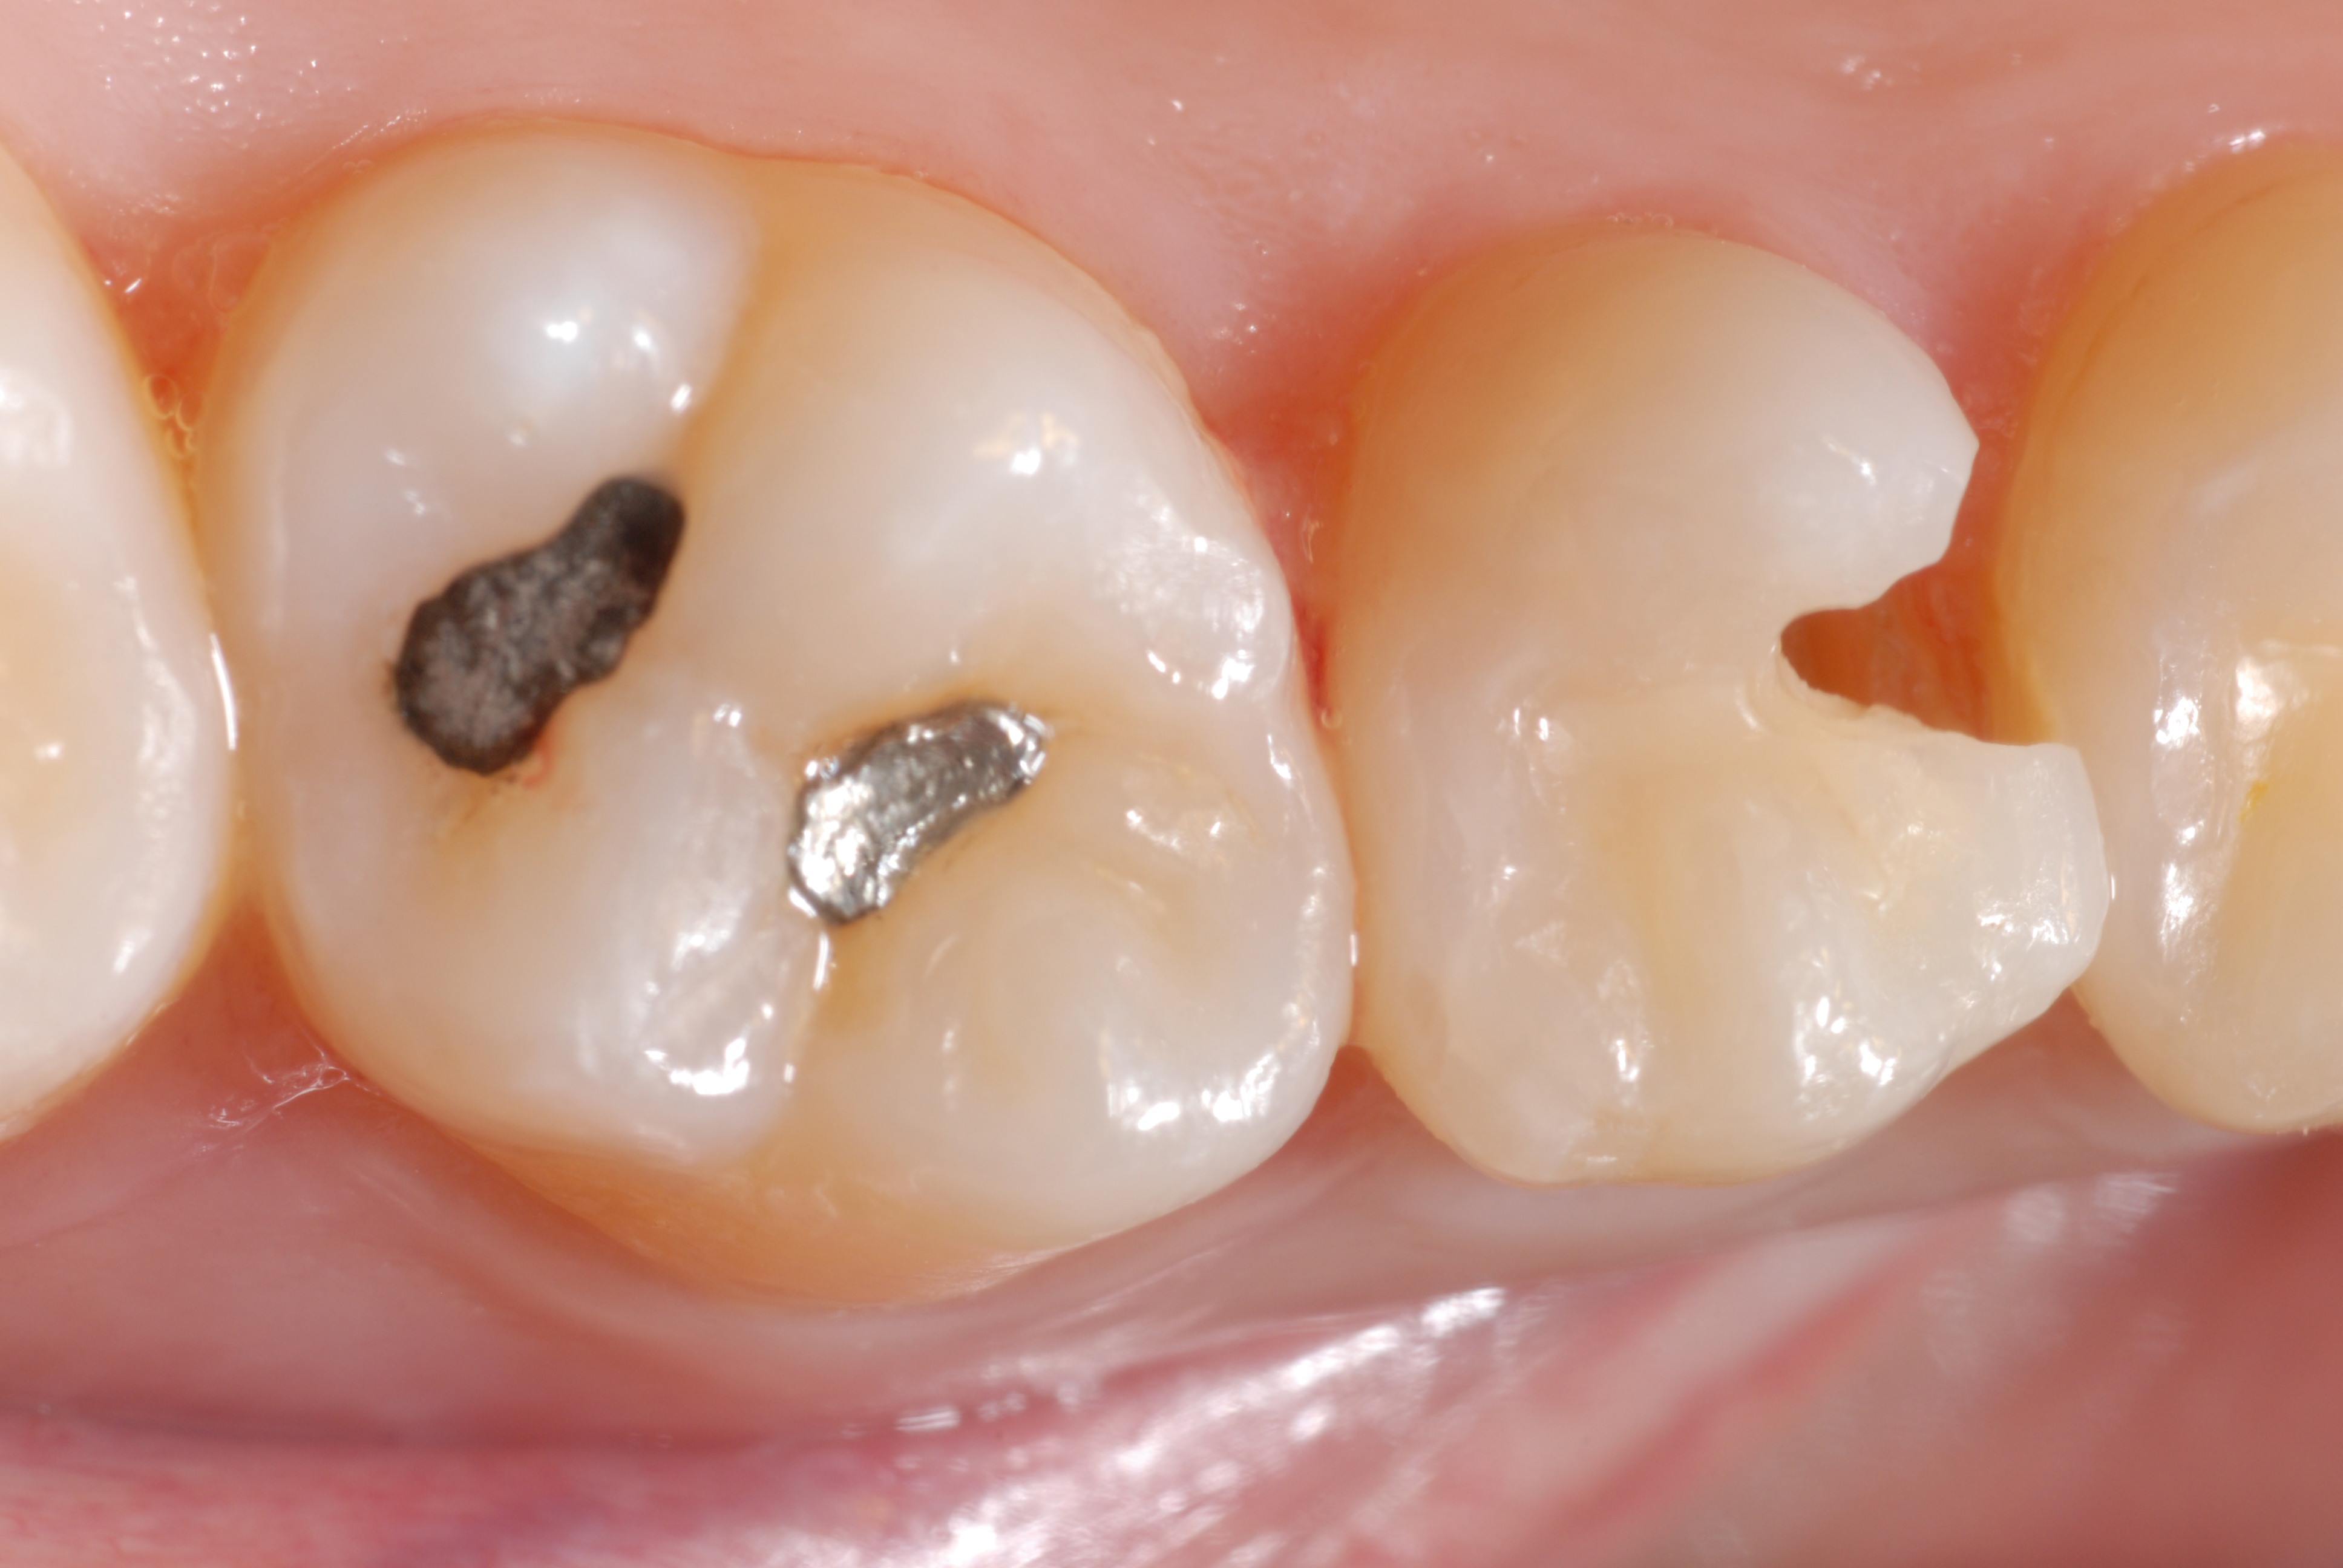

Une patiente s’est présentée au cabinet afin de faire évaluer l’état de santé de sa dentition. Les examens cliniques et radiologiques ont révélé un défect carieux avec carie active au niveau de la dent 15 (Ill. 1). La patiente souhaitait une restauration de la dent carieuse et, pour des raisons esthétiques, se montrait intéressée par le remplacement de l’obturation en amalgame au niveau de la dent 16.